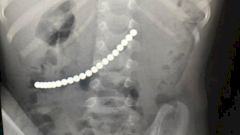

Малыш поступил с сильными болями в животе. В ходе диагностики был сделан рентген. Снимок показал, что между желудком и кишечником сцепились 20 шариков, которые проглотил ребенок.